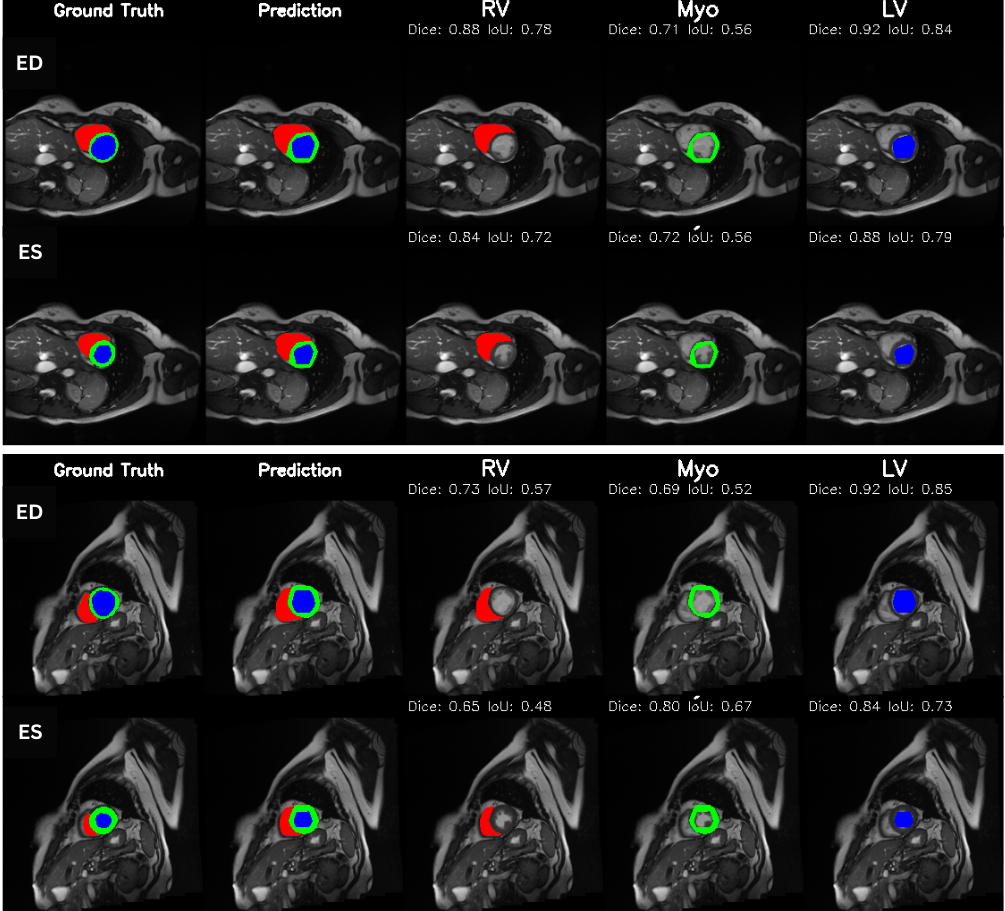

To evaluate cross–modality transfer, we perform few–shot fine tuning on the CAMUS echocardiography dataset, using only {5, 10, 20, 50} labeled samples from a single clinical site. Unlike MRI, ultrasound poses a significantly harder segmentation challenge due to acoustic artifacts, speckle noise, anisotropic contrast, and view–dependent anatomical deformation. Despite this domain gap, Figure 10 shows that PULSE progressively adapts to ultrasound geometry with increasing supervision. With only 5 labeled cases, the model produces coarse chamber boundaries and myocardium leakage, yet still recovers the global cardiac shape (mDice 0.612, mIoU 0.468). At 10 samples, segmentation accuracy improves substantially, with clear endocardial delineation and reduced basal drift (mDice 0.696, mIoU 0.556). Fine tuning on 20 cases leads to stable myocardium recovery (mDice 0.746), suggesting that the model internalizes modality–invariant structure once minimal supervision is available. At 50 cases, performance reaches near–MRI quality (mDice 0.815, mIoU 0.705), approaching full–data performance and producing visually crisp LV and RV walls even under ultrasound noise. These results demonstrate that PULSE can retain cardiac anatomical priors learned from MRI and rapidly transfer them to ultrasound with very limited supervisiona desirable property for deployment in low resource hospitals where complete annotation is rarely available. The smooth improvement across shots also reinforces the quantitative trend of Table 12, validating few–shot echocardiographic adaptation as a viable clinical pathway for real-world integration into emergency, bedside, and limited–annotation scenarios.